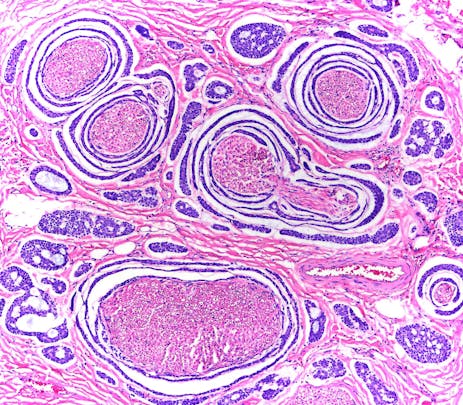

Adenoid Cystic Carcinoma Of Parotid Gland

This histologic section features prominent perineural invasion, one way many neoplasms are able to "spread."

The Muscle Spindle Apparatus

A photomicrograph of the skeletal muscle organ that prevents your biceps from shredding apart when you attempt to lift an automobile by the bumper. The stain is usual hematoxylin/eosin, the most common differential stain used in surgical pathology.